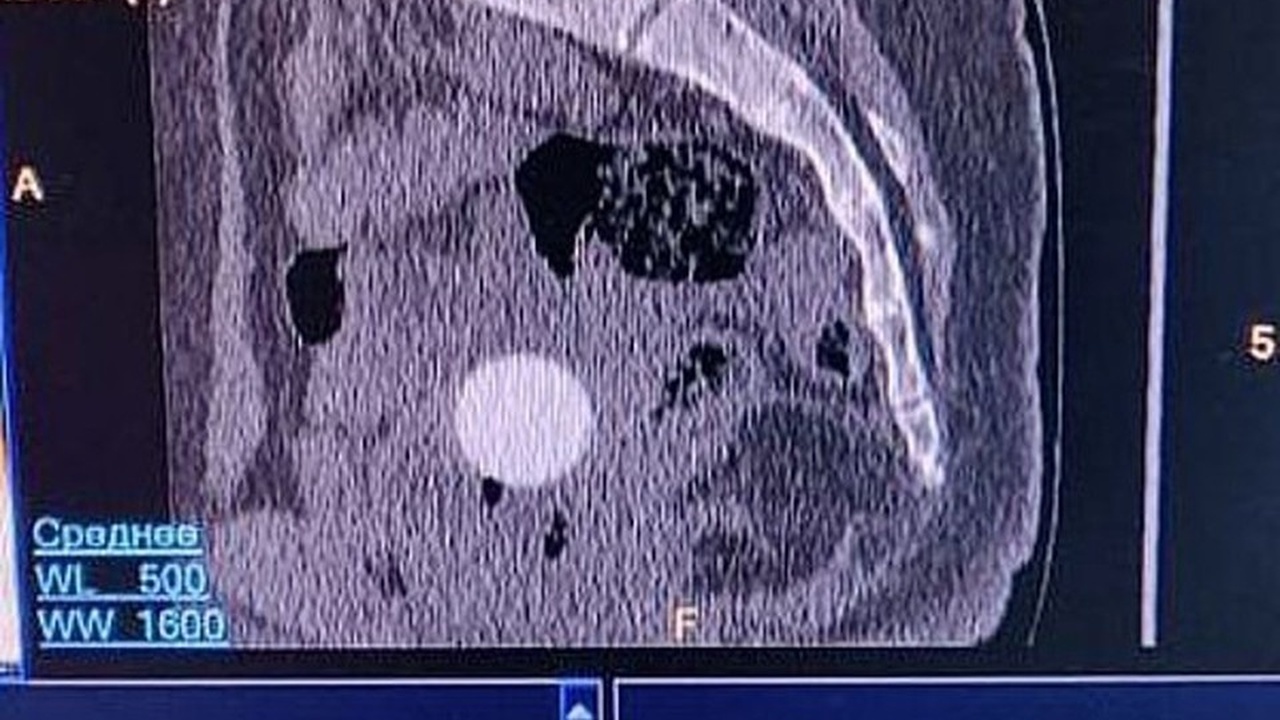

Первичный осмотр вызвал подозрение на перелом или другое повреждение копчика. Для уточнения диагноза была назначена компьютерная томография. Исследование показало неожиданное: помимо возможной травмы, в области малого таза обнаружился посторонний предмет.

Врач-гинеколог Елена Колотилова уточнила, что инородное тело находилось в верхнем отделе влагалища. Им оказался небольшой резиновый мячик, который смог проникнуть внутрь благодаря своей форме, но не мог самостоятельно выйти из-за анатомических особенностей детского организма.